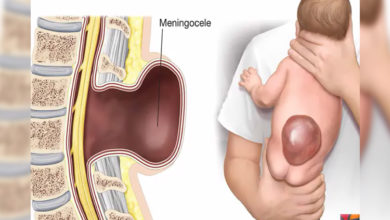

spina bifida